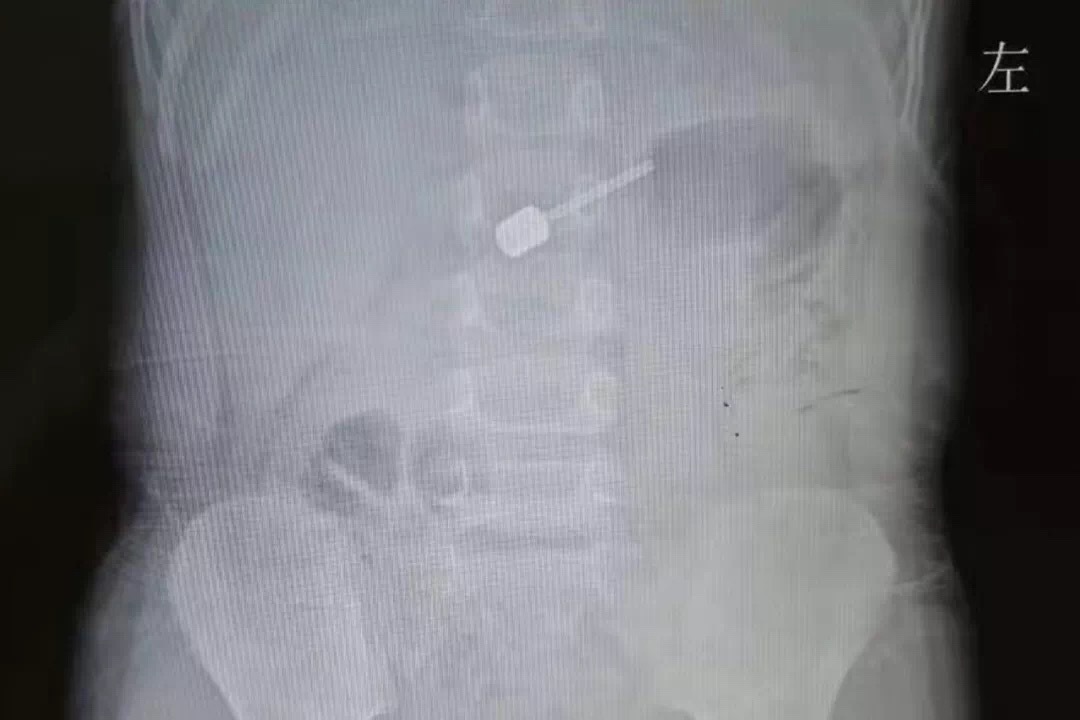

10月16日晚8点,一对焦急的父母带着自己近3岁的宝宝乐乐(化名)急匆匆地来到山东第一医科大学第二附属医院急诊科,原来,就在2小时前乐乐在玩耍时误吞了一枚球针,急诊科迅速为乐乐进行相关检查,并联系了儿外科值班医师宋波。宋波主治医师接诊了乐乐,详细询问情况后结合患儿查体以“消化道异物”收住入院,并立即联系李矿副主任医师和消化科为乐乐会诊,紧急取针。

消化科张晓伟副主任医师因为加班的缘故刚刚走进家门,就接到了儿外科请求会诊的电话,急忙赶回医院,了解情况后决定通过胃镜为乐乐取针。张晓伟介绍,当时乐乐的身体状态还是正常的,球针在乐乐的胃里本身取针难度不大,但是乐乐吞针后没有禁食,入院之前孩子刚刚吃了晚饭,胃内有大量食物,取针犹如大海捞针。

通过胃镜,张晓伟看到乐乐的胃里都是消化的食糜,根本看不到气针的位置,简直是浑水摸鱼、海里捞针,张晓伟操作动作轻柔,一点一点搜索,总算用套圈器将“肇事”的气针套住,小心翼翼地取了出来。取针过程有惊无险,看到异物被成功取出,家长悬着的心才终于放了下来。乐乐的妈妈害怕的哭出声来,并表示十分后悔,连连向医生道谢。一场小小气针引起的“动乱”,总算平息了下来。